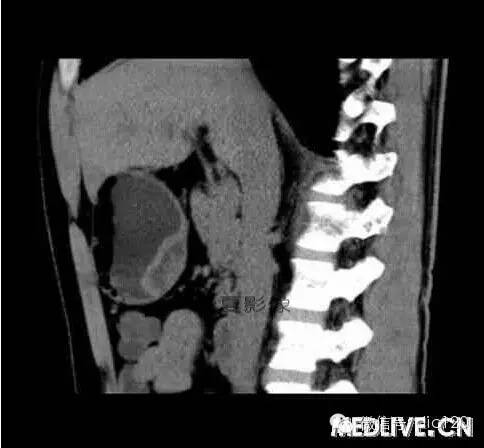

男,36歲,間斷性返酸噯氣3年,3個月前出現上腹疼痛,饑餓時加重。圖1-3為CT平掃,圖4-6分別為CT增強掃描的動脈期、門脈期和延遲期。

CT檢查可見胃幽門前區胃小彎側胃壁局限性增厚、隆起或伴凸向胃腔內的小結節灶,寬基地,境界光整,注射對比劑,增強掃描后,CT值可達50HU以上,與正常胰腺強化相仿。

胃迷走胰腺大多位在距幽門1-6cm的胃竇胃大彎側,粘膜下層內,為1-3cm大小的病灶。 與胃壁以寬基底相,增強掃描病灶表面覆蓋的黏膜明顯強化且連續,病灶內無明顯壞死,病變強化方式類似于正常胰腺組織;當病灶出現邊緣臍凹征或中央導管征時,對EP的診斷具有一定的特異性。